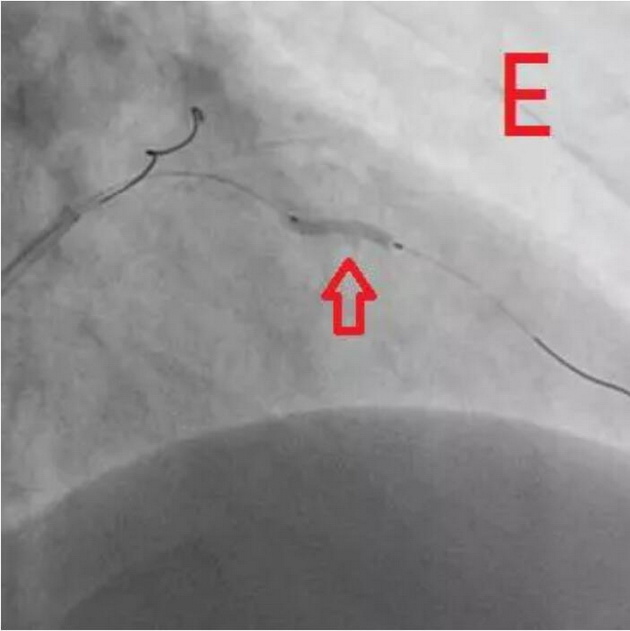

通过对该病变的分析,杨巍主任决定采用“振波球囊”对病变进行预处理。将振波球囊送至环形钙化处并启动4次,随后再次使用预扩球囊对病变处进行扩张,显示可以充分扩张(图E),继续IVUS检查,证实钙化斑块已经裂开(图F)。